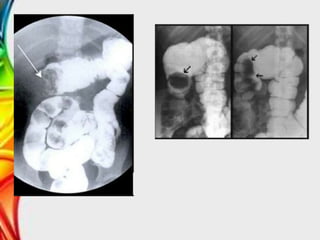

• Enemas de contraste (signo de Muelle)

Tratamiento

• La reducción de una invaginación aguda es un

procedimiento urgente que se realiza después del

diagnostico.

• La tasa de éxito de la reducción radiológica guiada

mediante fluoroscopía o ecografía es de alrededor del

80-95% en pacientes con invaginación ileocólica.

• Las perforaciones intestinales ocurren en el 0,5-2,5%

de los intentos de reducción con bario o hidrostática

(suero salino).

• La tasa de perforación de la reducción con aire varia

entre el 0,1 y el 0,2%.

Diagnóstico • Anamnesis yexploración física. • Ecografía (sensibilidad de 88%) – Masa tubular en proyecciones longitudinales – Aspecto en diana en proyecciones transversales • Enemas de contraste (signo de Muelle)

Tratamiento • La reducciónde una invaginación aguda es un procedimiento urgente que se realiza después del diagnostico. • La tasa de éxito de la reducción radiológica guiada mediante fluoroscopía o ecografía es de alrededor del 80-95% en pacientes con invaginación ileocólica. • Las perforaciones intestinales ocurren en el 0,5-2,5% de los intentos de reducción con bario o hidrostática (suero salino). • La tasa de perforación de la reducción con aire varia entre el 0,1 y el 0,2%.